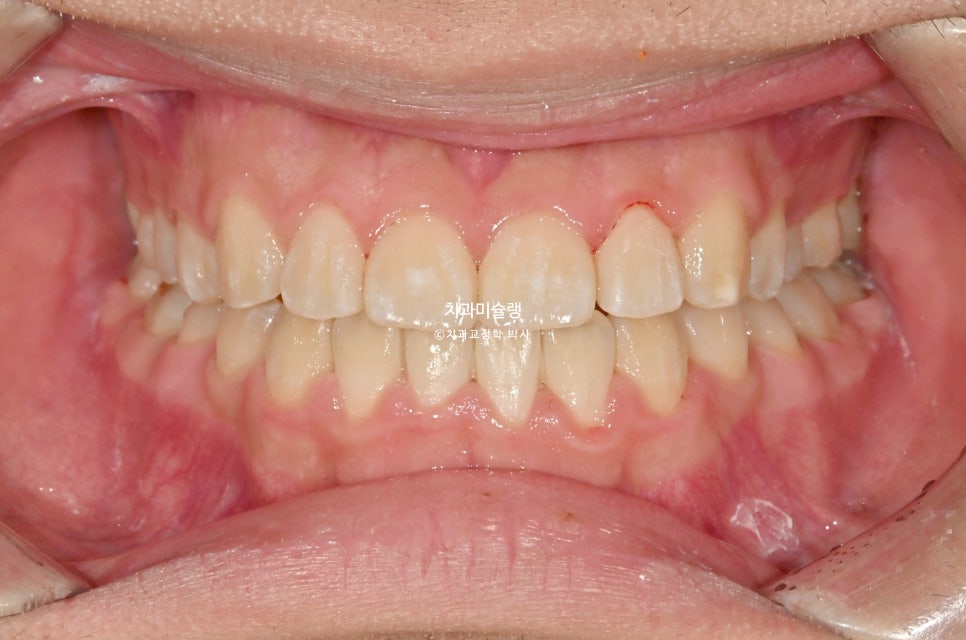

중심선은 잘 맞으며

어금니 교합은 우측은 거의1급 교합관계를 보입니다.